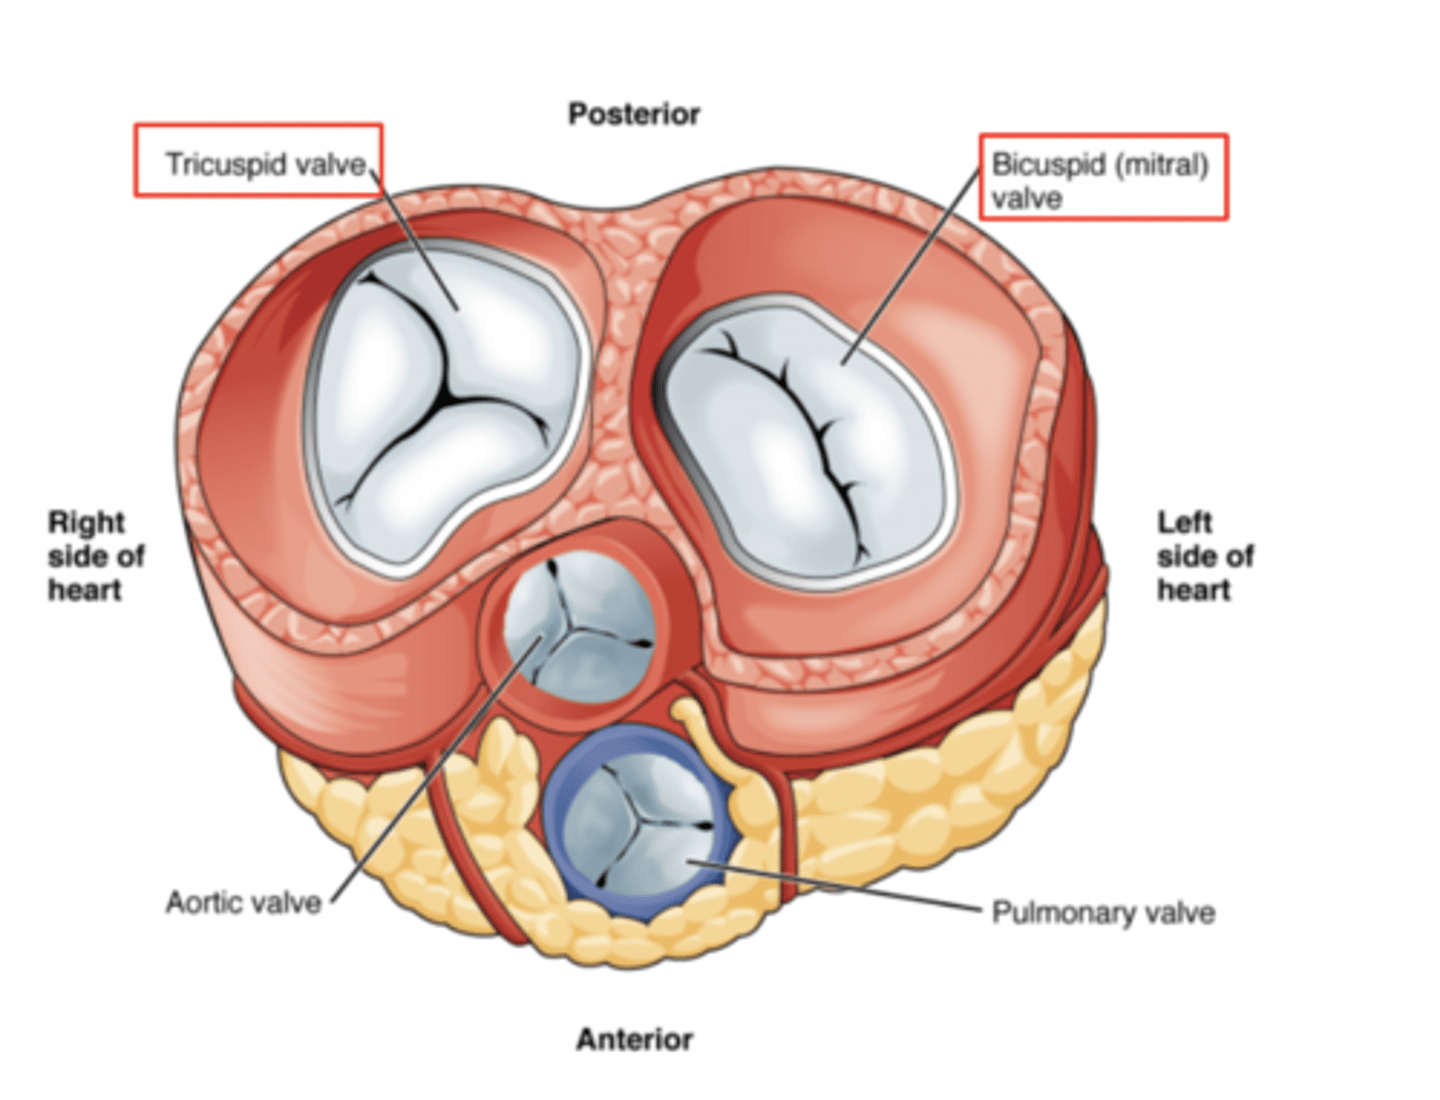

What are the valves separating atrium and ventricle?

. Tricuspid valve (right atrioventricular valve, 3 cusps)

. Mitral or bicuspid valve (left atrioventricular valve, 2 cusps)

AXIAL VIEW OF THE HEART

What are the four valves in the heart?

Tricuspid

Mitral or bicuspid

Pulmonary

Aortic

What valves are assuring the AV unidirectional flow?

Tricuspid (right)

Mitral or bicuspid (left)